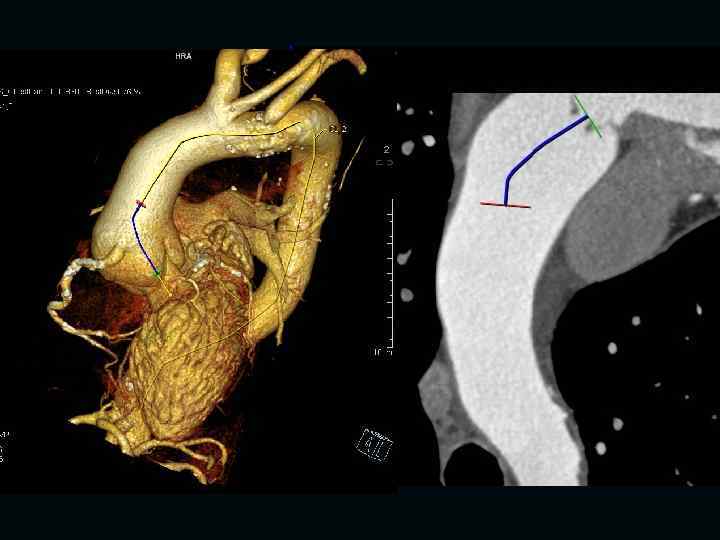

Исследование сосудов грудной клетки